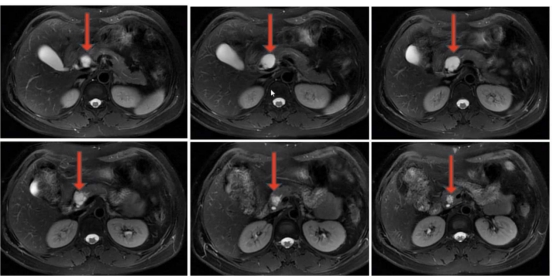

該患者體檢時發(fā)現(xiàn)胰腺囊性占位,因擔心外科手術創(chuàng)傷,遲遲未敢治療,隨著囊腫逐漸增大,出現(xiàn)了反復腹痛癥狀。來到衡陽市中心醫(yī)院消化內科就診后,醫(yī)生團隊為其完善超聲內鏡及囊液分析等檢查,明確診斷為胰腺粘液性囊腫,排除禁忌證后實施了聚桂醇滅活術。術后患者腹痛癥狀即刻緩解,住院3天便順利出院,復查時囊腫體積已明顯縮小,生活質量完全恢復正常。

胰腺作為人體消化系統(tǒng)的“核心引擎”,深藏于腹腔深處,其病變往往隱匿難察,治療難度頗高。胰腺囊性占位是臨床常見的胰腺病變,涵蓋假性囊腫、囊性腫瘤等多種類型,部分病變存在癌變風險,或因體積增大壓迫周圍器官引發(fā)腹痛、腹脹等不適,嚴重影響患者生活質量。以往傳統(tǒng)治療多依賴外科手術,創(chuàng)傷大、恢復慢,且可能伴隨胰漏、出血等并發(fā)癥,患者顧慮很多。現(xiàn)在,衡陽市中心醫(yī)院消化內科團隊推出超聲內鏡(EUS)引導下胰腺囊性占位聚桂醇滅活術,為患者帶來精準、安全、高效的診療新選擇。該技術“超級微創(chuàng)”,將超聲內鏡的“精準導航”與聚桂醇的“溫和消融”完美結合,適用于直徑>1cm、有癥狀的胰腺囊性病變,以及高齡、合并基礎疾病無法耐受外科手術或拒絕手術的患者。手術全程在超聲內鏡實時引導下進行,醫(yī)生可清晰洞察病灶位置、大小及與周圍血管、器官的解剖關系,通過細針穿刺精準穿刺至囊腔內,抽凈囊液后注入聚桂醇硬化劑,實現(xiàn)對病灶的靶向滅活。整個手術僅需30分鐘左右,全程微創(chuàng),無需開腹,僅留下細微穿刺痕跡,有效避免了傳統(tǒng)手術對胰腺及周圍組織的損傷,最大程度保留胰腺正常生理功能。

聚桂醇滅活術是消化介入領域的前沿技術,憑借其安全性高、不良反應少的優(yōu)勢,逐步取代傳統(tǒng)消融劑成為囊性病變治療的優(yōu)選方案。與傳統(tǒng)無水乙醇消融相比,聚桂醇通過改變細胞膜表面能量分布,破壞囊壁內皮細胞,引發(fā)無菌性炎癥及纖維組織增生,最終實現(xiàn)囊腔閉合,不僅消融效果確切,且術后腹痛、醉酒樣反應等不良反應發(fā)生率極低,總體并發(fā)癥發(fā)生率僅4.3%,顯著提升了治療的安全性與患者耐受性。臨床研究顯示,該技術總體消融有效率高達94.7%,隨訪12個月以上的長期有效率亦達79.4%。